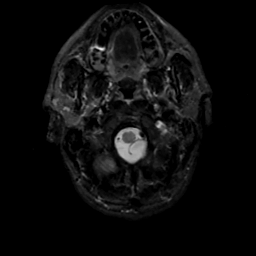

MR Study #15, June 9, 1991 -- Slice #2

[Home][Help][Clinical][Tour 1][Tour 2] Slice 2